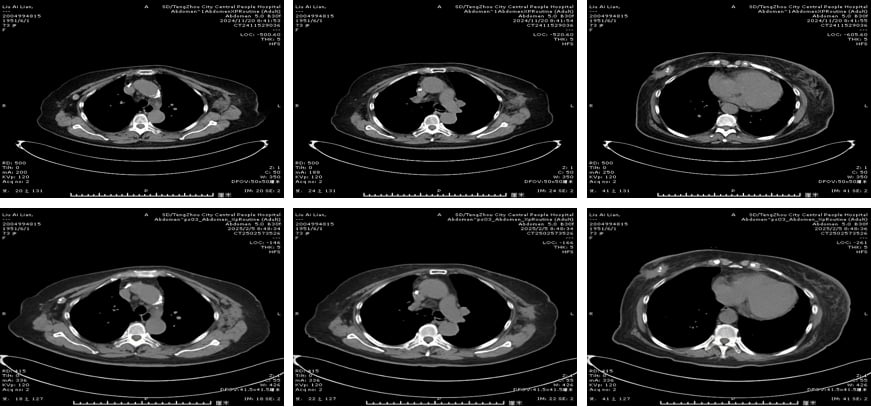

三线治疗(2023.3-2024.7):对侧乳腺新发病灶,双靶联合化疗再出击

2023年3月,患者左乳发现新发肿物及腋窝淋巴结肿大,经穿刺活检证实为左乳浸润性导管癌,同样是HER2阳性。考虑到患者年龄及基础疾病,她拒绝了手术。医生再次调整方案,采用了帕妥珠单抗、伊尼妥单抗双靶联合卡培他滨化疗。帕妥珠单抗是另一种HER2靶向药物,与曲妥珠单抗作用机制互补,形成双重阻断,能更有效地抑制HER2信号通路。伊尼妥单抗也是一种新型的HER2靶向药物。这一方案持续了10个周期,左乳肿物明显缩小,腋窝淋巴结也得到控制,评估为部分缓解(PR)。

四线治疗(2024.7-2025.2):ADC药物登场,恩美曲妥珠单抗显身手

2024年7月,患者因冠心病、房性早搏就诊心内科,治疗一度中断。待心脏问题稳定后,医生引入了抗体偶联药物(ADC)——恩美曲妥珠单抗(T-DM1)。ADC药物是一种“导弹式”的精准打击武器,它将靶向抗体(如抗HER2抗体)与高效化疗药物(如DM1)偶联,通过抗体识别癌细胞表面的靶点,将化疗药物精准递送至癌细胞内部,减少对正常细胞的损伤,从而提高疗效并降低全身性副作用。经过4个周期的T-DM1治疗,患者病情稳定(SD),仅出现轻度乏力、血小板减少,耐受性良好。

五线治疗(2025.3-至今):德曲妥珠单抗持续抗癌,疗效显著

2025年3月,患者开始接受目前最先进的ADC药物之一——德曲妥珠单抗(T-DXd)治疗。德曲妥珠单抗同样是ADC药物,它将抗HER2抗体与拓扑异构酶I抑制剂偶联,具有更高的药物抗体比(DAR),意味着每个抗体携带的化疗药物更多,且其化疗载荷在肿瘤微环境中释放后,还能穿透细胞膜,对周围的癌细胞产生“旁观者效应”,进一步增强抗肿瘤活性。截至目前,患者已接受9个周期的T-DXd治疗,左侧腋窝淋巴结较前变小,左乳不规则软组织密度范围缩小,病情持续稳定,且不良反应轻微,耐受性良好。这再次证明了新一代ADC药物在HER2阳性乳腺癌后线治疗中的卓越疗效和安全性。